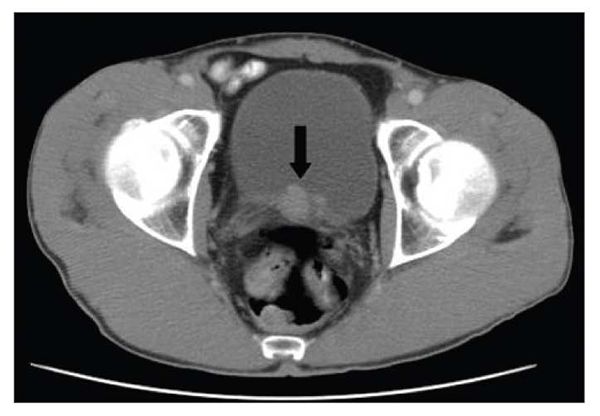

Figure 2. Focal thickening of the right lateral aspect of the bladder wall can be seen in this CT scan. A polypoid filling defect within the bladder was detected on delayed imaging. A 2 × 3-cm diverticulum filled with tumor was extracted by transurethral resection. Pathological examination of the tissue showed a papillary urothelial carcinoma with no muscularis involvement. The patient was a 51-year-old HIV-infected man.

A CT scan of the abdomen and pelvis showed focal thickening of the right lateral wall of the bladder close to the trigone, with a polypoid defect in the inferior aspect (Figure 2). A 2 × 3-cm diverticulum filled with tumor was extracted by transurethral resection. Pathological examination of the tissue showed low-grade, T1 papillary urothelial carcinoma with no muscularis involvement.

Multiple surveillance cystoscopy done at 6-month intervals over 2 years revealed papillary tumors, which were resected. Pathological studies showed low-grade, T1 papillary carcinoma. Cystoscopy done at 1 year showed multiple bladder tumors, which were removed from the bladder neck, left lateral wall, and posterior wall. Pathological examination revealed a low-grade tumor with extension into the lamina propria. Repeated cystoscopy done at 18 months showed multiple bladder tumors, and pathological examination showed low-grade tumor without muscularis involvement. Two years after diagnosis, cystoscopy revealed multiple tumors. Results from transurethral resection ranged from carcinoma in situ to high-grade papillary urothelial cancer. The patient’s CD4+ cell count was 546/μL, and his HIV RNA level was 641 copies/mL.